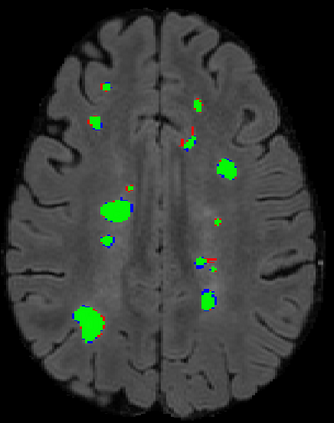

The detection of new multiple sclerosis (MS) lesions is an important marker of the evolution of the disease. The applicability of learning-based methods could automate this task efficiently. However, the lack of annotated longitudinal data with new-appearing lesions is a limiting factor for the training of robust and generalizing models. In this work, we describe a deep-learning-based pipeline addressing the challenging task of detecting and segmenting new MS lesions. First, we propose to use transfer-learning from a model trained on a segmentation task using single time-points. Therefore, we exploit knowledge from an easier task and for which more annotated datasets are available. Second, we propose a data synthesis strategy to generate realistic longitudinal time-points with new lesions using single time-point scans. In this way, we pretrain our detection model on large synthetic annotated datasets. Finally, we use a data-augmentation technique designed to simulate data diversity in MRI. By doing that, we increase the size of the available small annotated longitudinal datasets. Our ablation study showed that each contribution lead to an enhancement of the segmentation accuracy. Using the proposed pipeline, we obtained the best score for the segmentation and the detection of new MS lesions in the MSSEG2 MICCAI challenge.